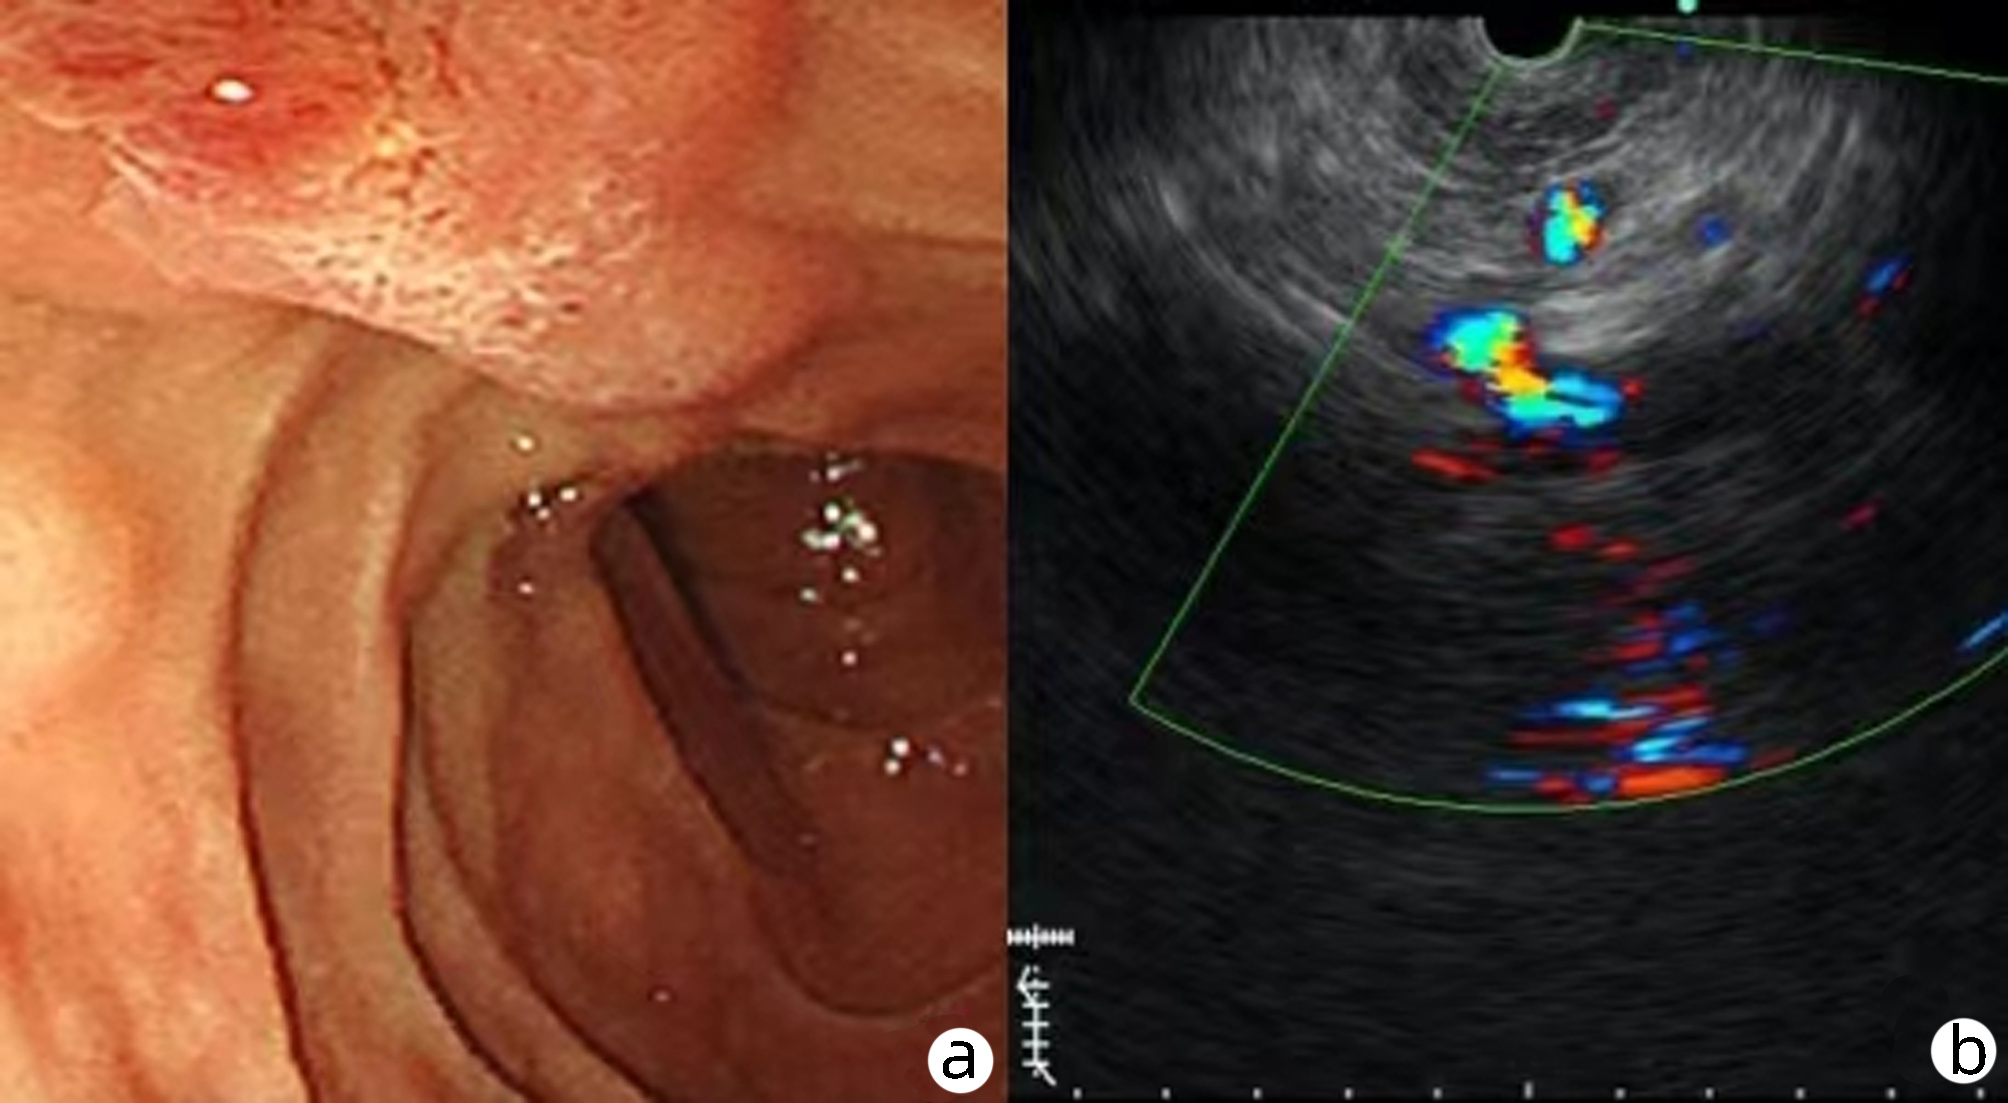

Selection of treatment regimens for pancreatic duct stones: A comparative analysis

Jinbin DONG, Weibing FANG, Yihai SHI

2022, 38(11): 2558-2564. DOI: 10.3969/j.issn.1001-5256.2022.11.023

Abstract(839) HTML (936) PDF (2050KB)(88)

Abstract:

Objective  To investigate the clinical efficacy of endoscopic retrograde cholangiopancreatography (ERCP), laparoscopy, and laparotomy in the treatment of pancreatic duct stones (PDS) by collecting related clinical data, to summarize the experience in selecting treatment regimens for PDS, and to further explore feasible treatment regimens that could maximize and optimize the benefits of PDS patients.  Methods  A retrospective analysis was performed for the clinical data of 131 PDS patients who were treated in Gongli Hospital Affiliated to Naval Medical University from June 2014 to December 2018, and according to the surgical procedure, they were divided into ERCP group with 69 patients, laparoscopy group with 32 patients, and laparotomy group with 30 patients. Related indices were monitored before and after treatment, and surgical outcome was compared between the laparoscopy group and the laparotomy group. The independent samples t-test was used for comparison of normally distributed continuous data between two groups; a one-way analysis of variance was used for comparison between multiple groups, and the least significant difference t-test or the SNK-q test was used for further comparison between two groups. The Mann-Whitney U test was used for comparison of continuous data with skewed distribution between two groups, and the Kruskal-Wallis H test was used for comparison between multiple groups. An repeated measures analysis of variance and the Friedman test were used for comparison of related indices before and after surgery, and the chi-square test was used for comparison of categorical data between groups.  Results  Among the 131 PDS patients, there were 40 patients with type Ⅰ PDS, 76 with type Ⅱ PDS, and 15 with type Ⅲ PDS. There was no significant difference in the distribution of main surgical methods between the laparoscopy group and the laparotomy group (χ2=1.93, P > 0.05). There were significant differences between the laparoscopy group and the laparotomy group in the dynamic changes of white blood cell count, C-reactive protein, procalcitonin, and Homeostasis Model Assessment of Insulin Resistance after surgery (F=24.68, χ2=227.66, F=45.37, F=106.71, all P < 0.05). Compared with the laparotomy group, the laparoscopy group had significantly shorter time of operation, significantly lower intraoperative blood loss, significantly shorter time to first flatus after surgery, a significantly lower frequency of use of pain-relieving drugs, shorter time to extraction of abdominal drainage tube, lower incidence rates of short-term postoperative complications, and a significantly shorter length of postoperative hospital stay (t=-4.80, t=-9.43, Z=-6.78, t=-11.59, Z=-6.77, χ2=9.24, t=-3.60, all P < 0.05). The incidence rate of short-term postoperative complications was 24.64% in the ERCP group, 28.13% in the laparoscopy group, and 66.67% in the laparotomy group, with a significant difference between groups (χ2=17.12, P < 0.05), and the ERCP group and the laparoscopy group had a significantly lower incidence rate of short-term postoperative complications than the laparotomy group (χ2=15.78 and 9.24, P < 0.05 and P=0.02). The treatment response rate was 91.30% in the ERCP group, 93.75% in the laparoscopy group, and 73.33% in the laparotomy group, with a significant difference between the three groups (χ2=7.70, P=0.02), and the ERCP group and the laparoscopy group had a significantly better response rate than the laparotomy group (χ2=5.56 and 4.77, P=0.02 and 0.03).  Conclusion  ERCP is the preferred method for minimally invasive treatment of some patients with type Ⅰ/Ⅱ PDS and is safe and effective with few serious complications. Surgical operation is an important method for the treatment of complex PDS, but with complicated techniques and difficult operation. Compared with laparotomy, laparoscopy has the advantages of small trauma, few serious complications, and high abdominal pain remission rate and can significantly shorten the time of operation, reduce intraoperative blood loss, and shorten the length of postoperative hospital stay. Therefore, laparoscopy should be the preferred regimen for the treatment of complex PDS.